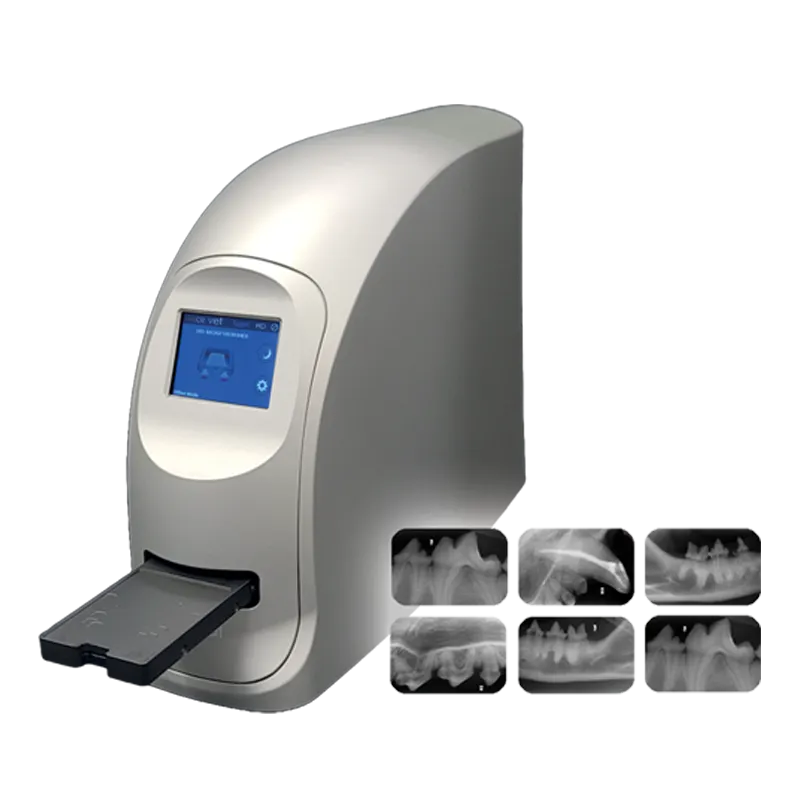

CR (Computed Radiography)

CR scanner

High detail resolution depending on imaging plate (sizes 0, 1, 2, 3, 4) and scanner

Scan time per imaging plate (seconds range)

Compact tabletop device; stationary or flexibly positionable

Multi-format intraoral imaging plates (0–4)